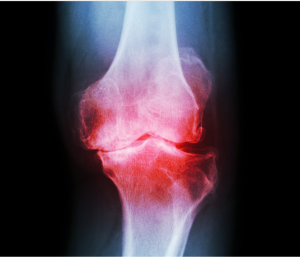

Fisioterapia ed agopuntura per l’osteoartrite dell ginocchio

Efficacia dell’agopuntura, della riabilitazione con esercizio fisico e della loro combinazione nel trattamento dell’osteoartrite del ginocchio: Uno studio controllato randomizzato

Obiettivo

Valutare l’efficacia dell’agopuntura, della riabilitazione con esercizio fisico e della loro combinazione nel trattamento dell’osteoartrite del ginocchio (KOA).

Abbiamo condotto questo studio randomizzato e controllato su pazienti con KOA, che abbiamo assegnato in modo casuale a tre gruppi: agopuntura (AP), riabilitazione con esercizio fisico (ER) o una combinazione di agopuntura e riabilitazione con esercizio fisico (AE).…